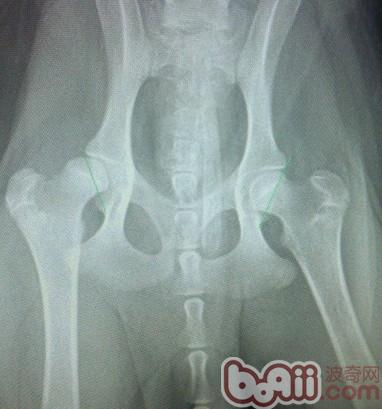

此X光片为数码片,通过图中的绿色测量线可发现左侧的股骨头和右侧的股骨头在关节窝里的面积明显不同,但是由于拍摄此片时患犬未镇静麻醉,所以摆位不正,不能作为确诊的理由,所以建议还是在患犬肌肉放松的情况下拍片。